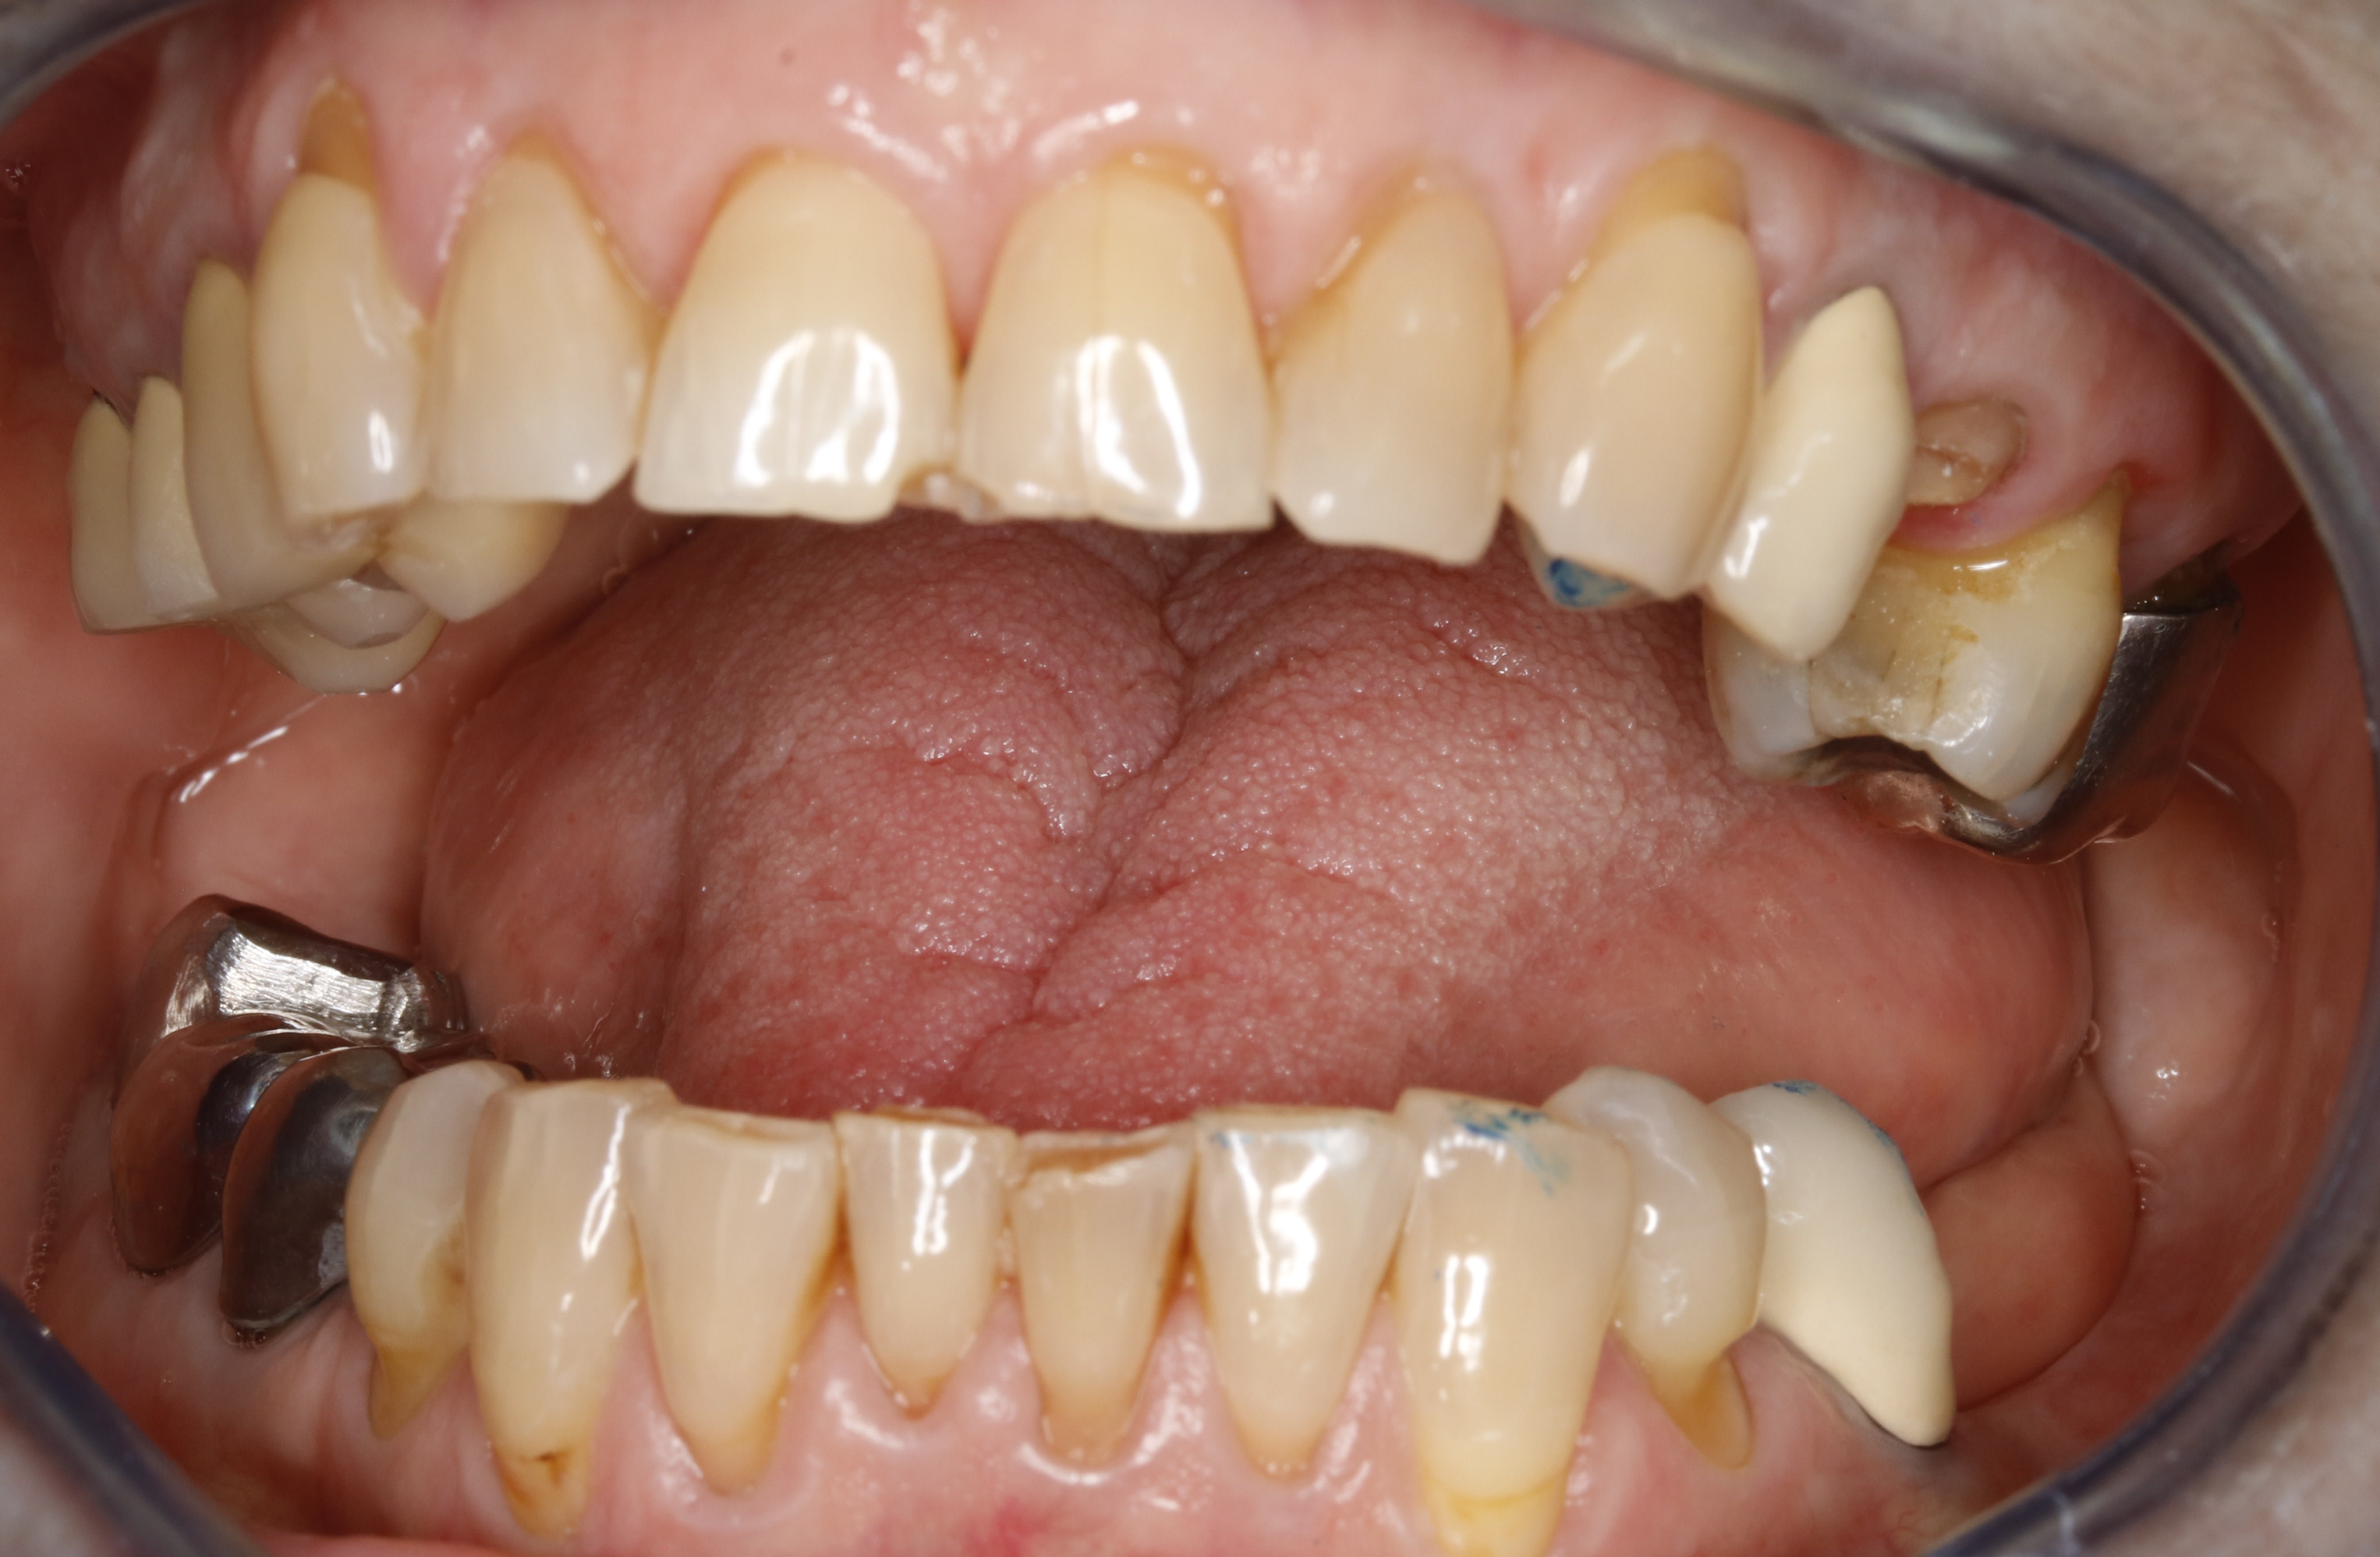

encore un cas .

une belle crête proxi , mais cette fois ci qui ne gène pas la rétropropulsion mais la propulsion .

2 eme particularité les appuis droite gauche sont dissymétriques ,( ça a une importance )

à cause de tout ça elle a explosé sa 25 qui etait couronnée depuis peu apparemment .

bien regardons sa position nocturne

son seul échappatoire , est non pas de partir en avant puisqu elle ne peut pas , pour cause de son escalier énorme . non pas de partir à droite puisqu il manque des dents et donc un calage .

elle ne peut partir qu a gauche , comme sur la photo .

et en allant à gauche ( vous la voyez la facette d appuis en mesio vest de 46 ? ) elle a le choix de son callage , par contre à droite elle n a pas le choix ce sera forcement sur la 25 afin d avoir le trepied le plus écarté possible pour une raison de stabilité évidente .